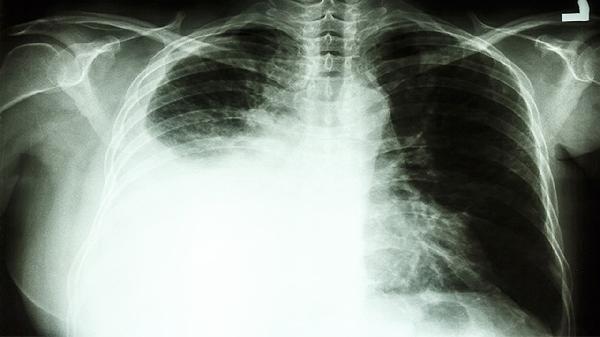

CEA显著升高需警惕恶性肿瘤可能。非小细胞肺癌患者CEA阳性率较高,当肿瘤侵犯支气管黏膜或发生远处转移时,CEA数值可能急剧上升,需结合胸部CT和病理活检明确诊断。结直肠癌患者随着肿瘤体积增大和分期进展,CEA释放入血增多,同时可能出现便血、肠梗阻等症状。胃癌晚期伴腹膜转移时CEA水平往往明显增高,胃镜取组织病理检查是确诊依据。

发现CEA升高应完善影像学和病理学检查。建议进行胸部低剂量CT筛查肺部病变,胃肠不适者需做胃肠镜评估消化道情况,同时检测CA199、CA724等其他肿瘤标志物辅助判断。日常需戒烟限酒,避免过度焦虑,定期复查监测指标变化趋势,由专科医生综合临床表现和其他检查结果进行诊断。